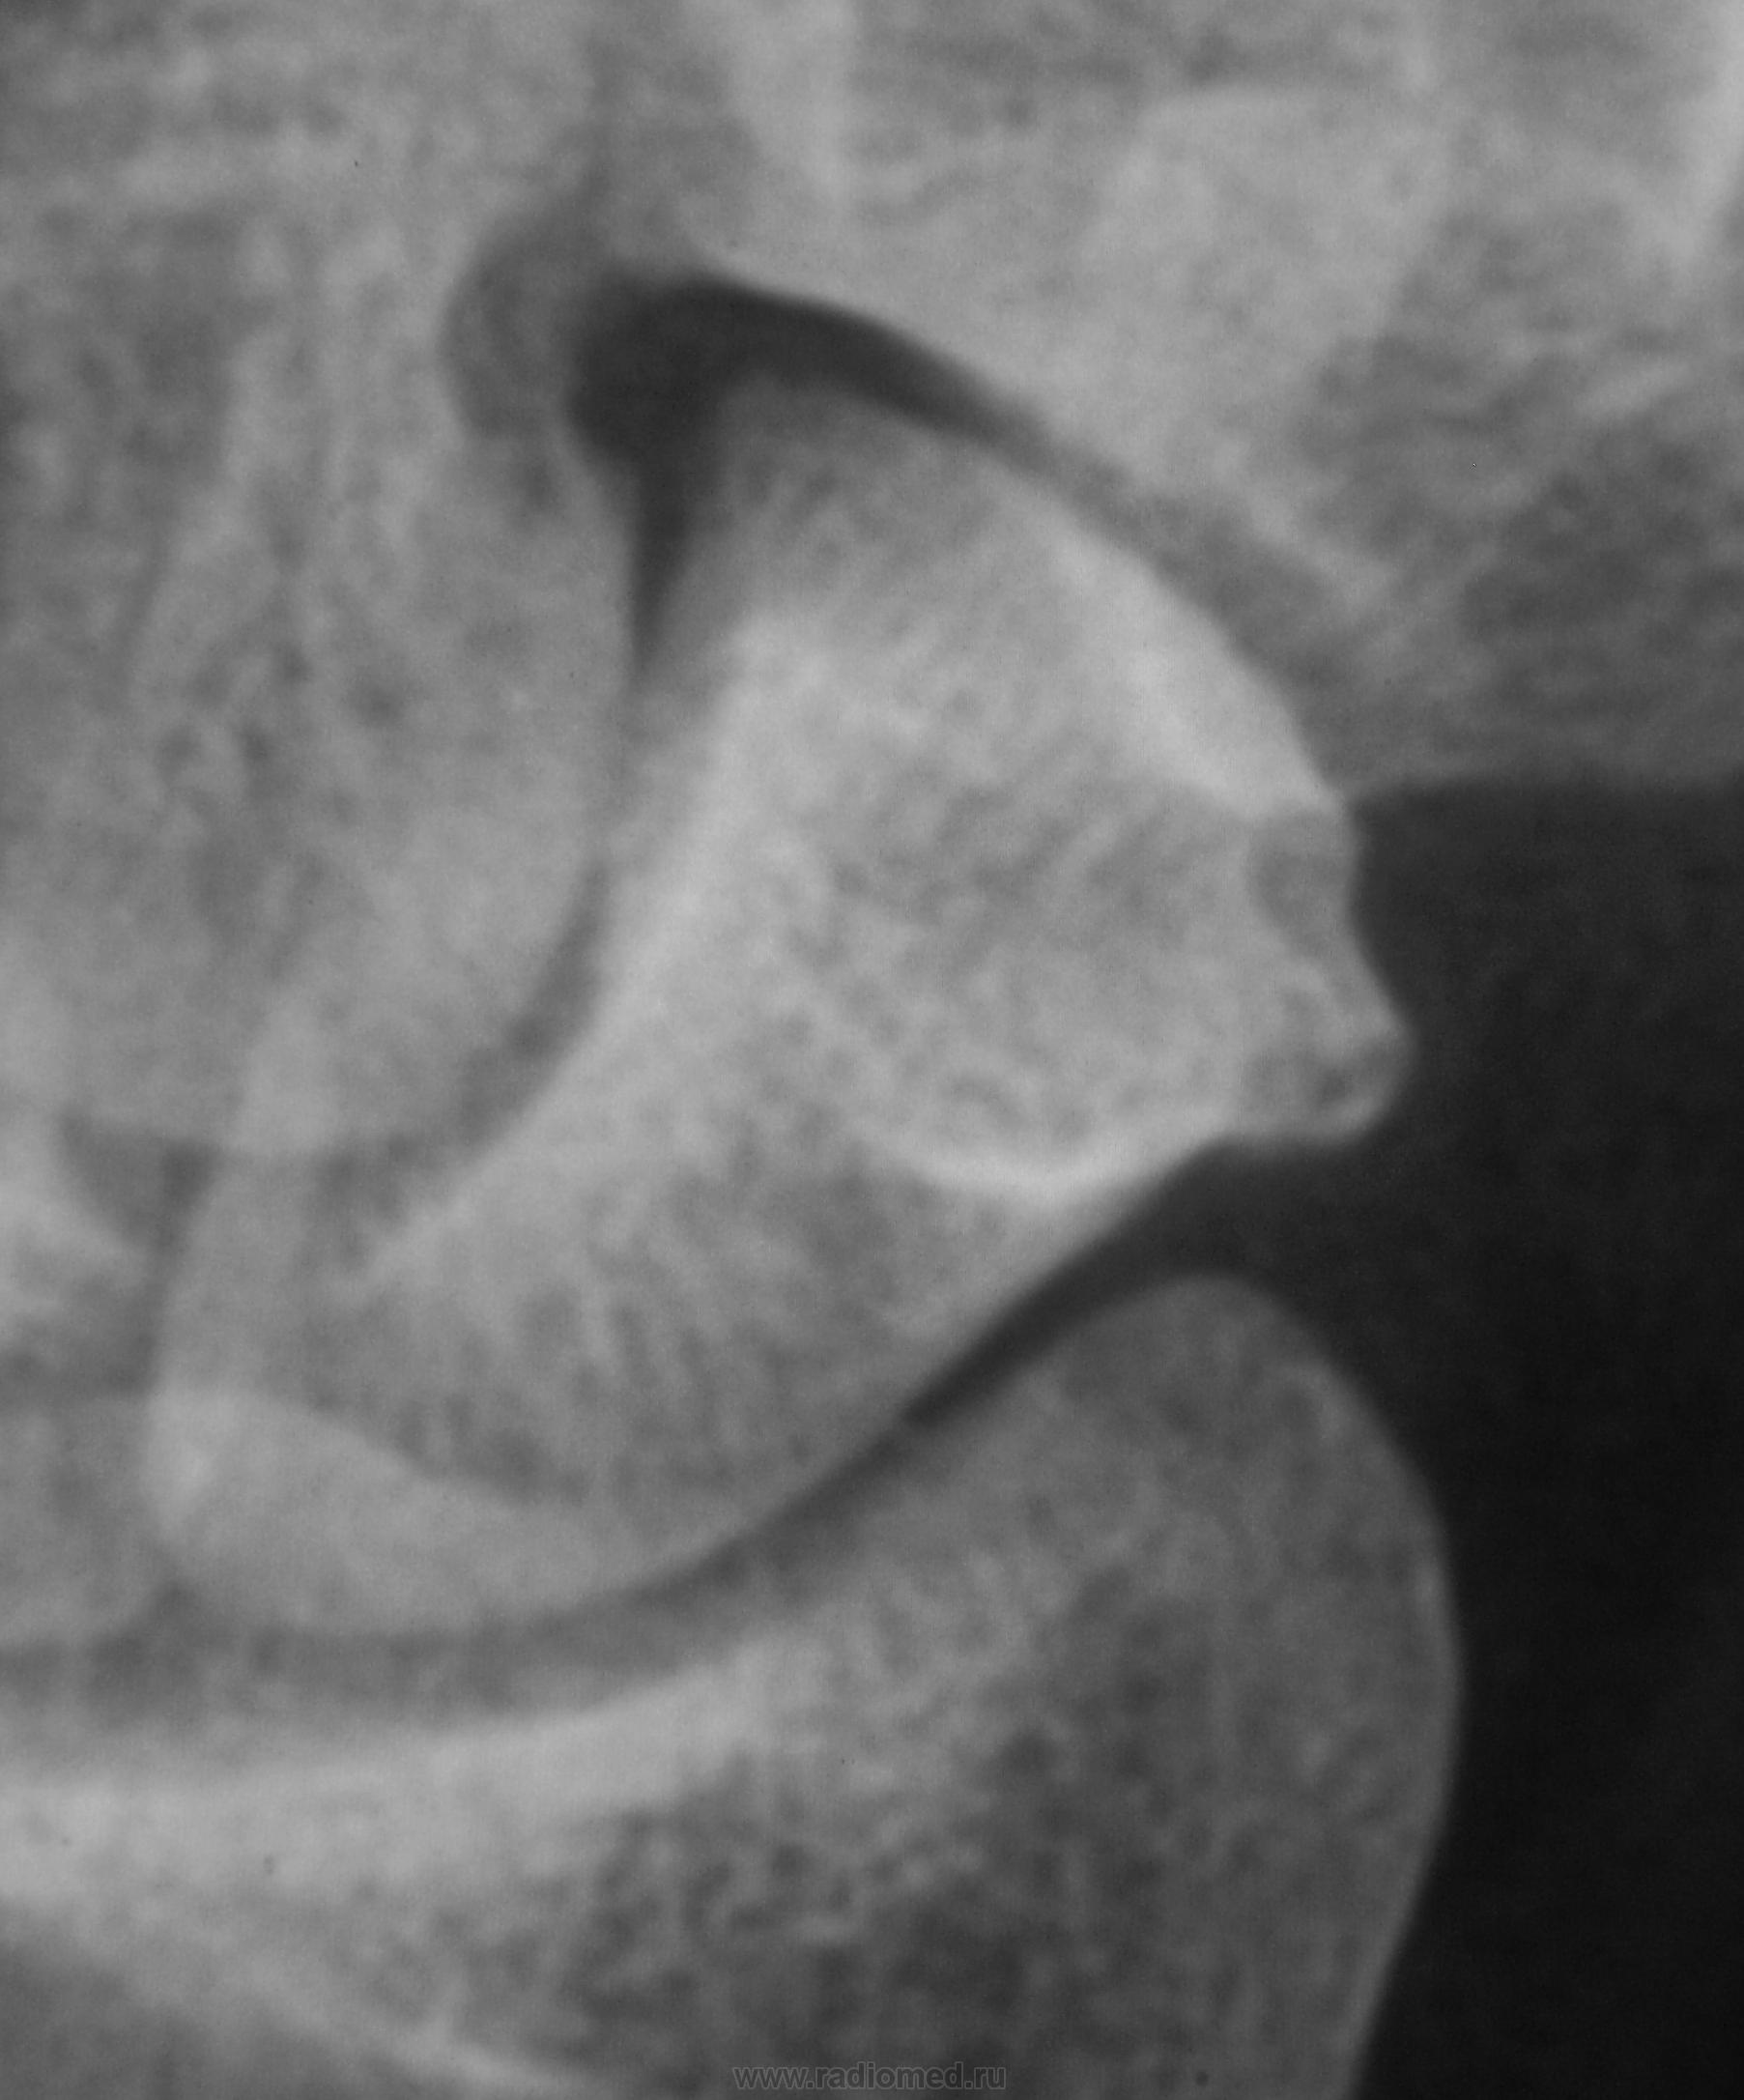

Пациент направлен хирургом на рентгенографию лучезапястного сустава с подозрением на артроз.

Какие мнения будут уважаемые коллеги?

tuberculum ossis scaphoidei

И что этот бугорок может вызывать боли в суставе?